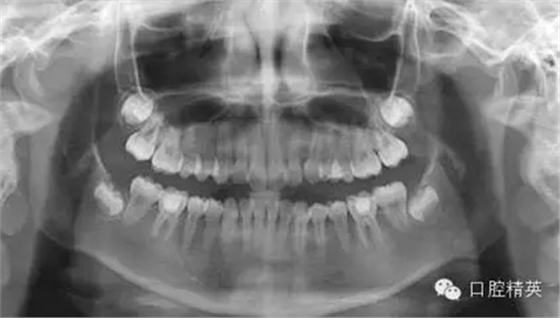

前幾天的一個外院斷針轉(zhuǎn)診來的客人,14歲在校女生,數(shù)年前齲齒充填,一個月前牙痛先后在2家診所診治,未果。。。

后來本診所求診,以下為取斷針的部分影像:

1,術(shù)前X-ray,常規(guī)術(shù)前攝片,為患者和自己保留一份客觀記錄。